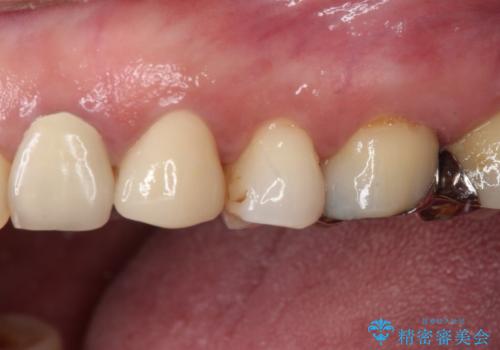

補綴治療では歯の形態を犬歯に近づけ、将来的な歯根への負担を軽減できるようにしました。

補綴後6ヶ月経過しレントゲンを撮影したところ、歯根周辺に病変認められず、良好な経過をたどっていることが分かりました。